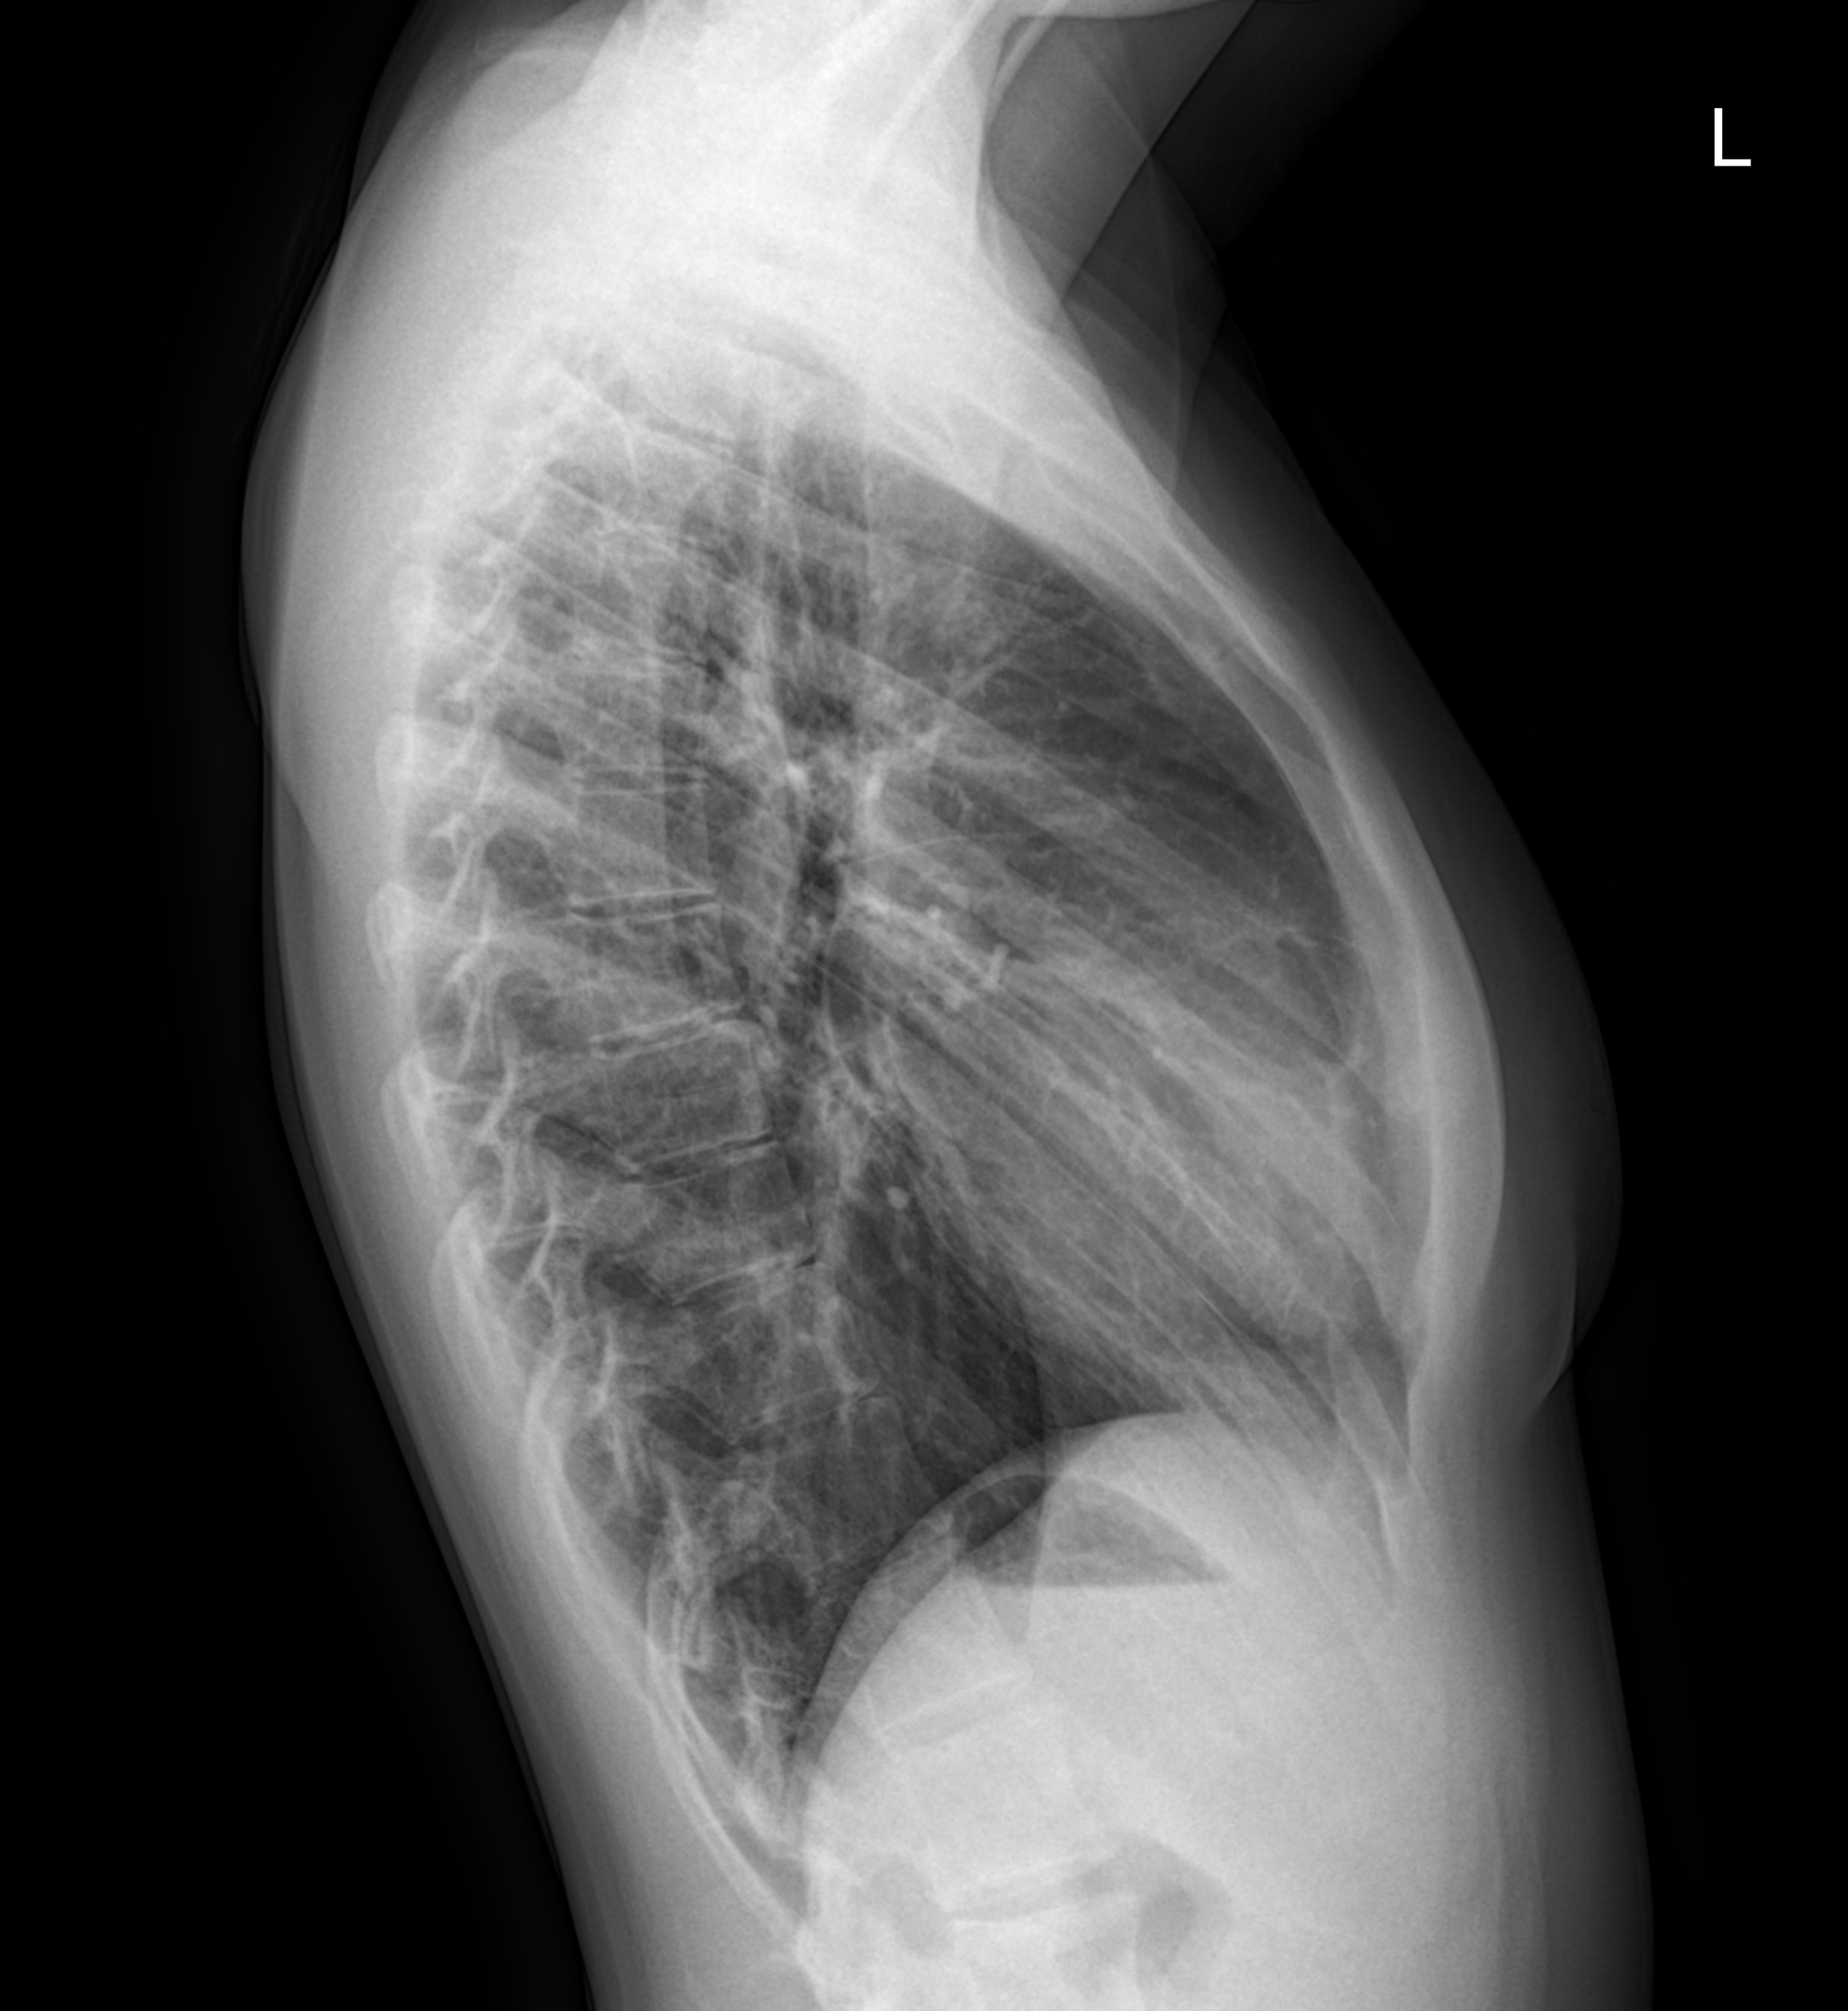

Так, начнем с рентгенографии. Данный метод исследования, как правило, используют для проведения обзорных исследований (скрининга), чтобы установить факт наличия патологии легочной ткани. В своей основе, такое исследование использует рентген-лучи и считывает разность прохождения данных лучей через структуры организма. Разность в прохождении лучей формируется за счет неоднородности плотностных характеристик структур организма. Рентгенография легких как правило делается в двух проекциях: фронтальной и боковой. На рентген-пленке хорошо видно наличие патологических изменений легочной системы (при пневмонии поражение легких 3 и 4 степени, туберкулез, плеврит и т.д.), а вот более мелкие патологические процессы скорее всего будут не визуализированы в виду феномена наложения теней от других органов.